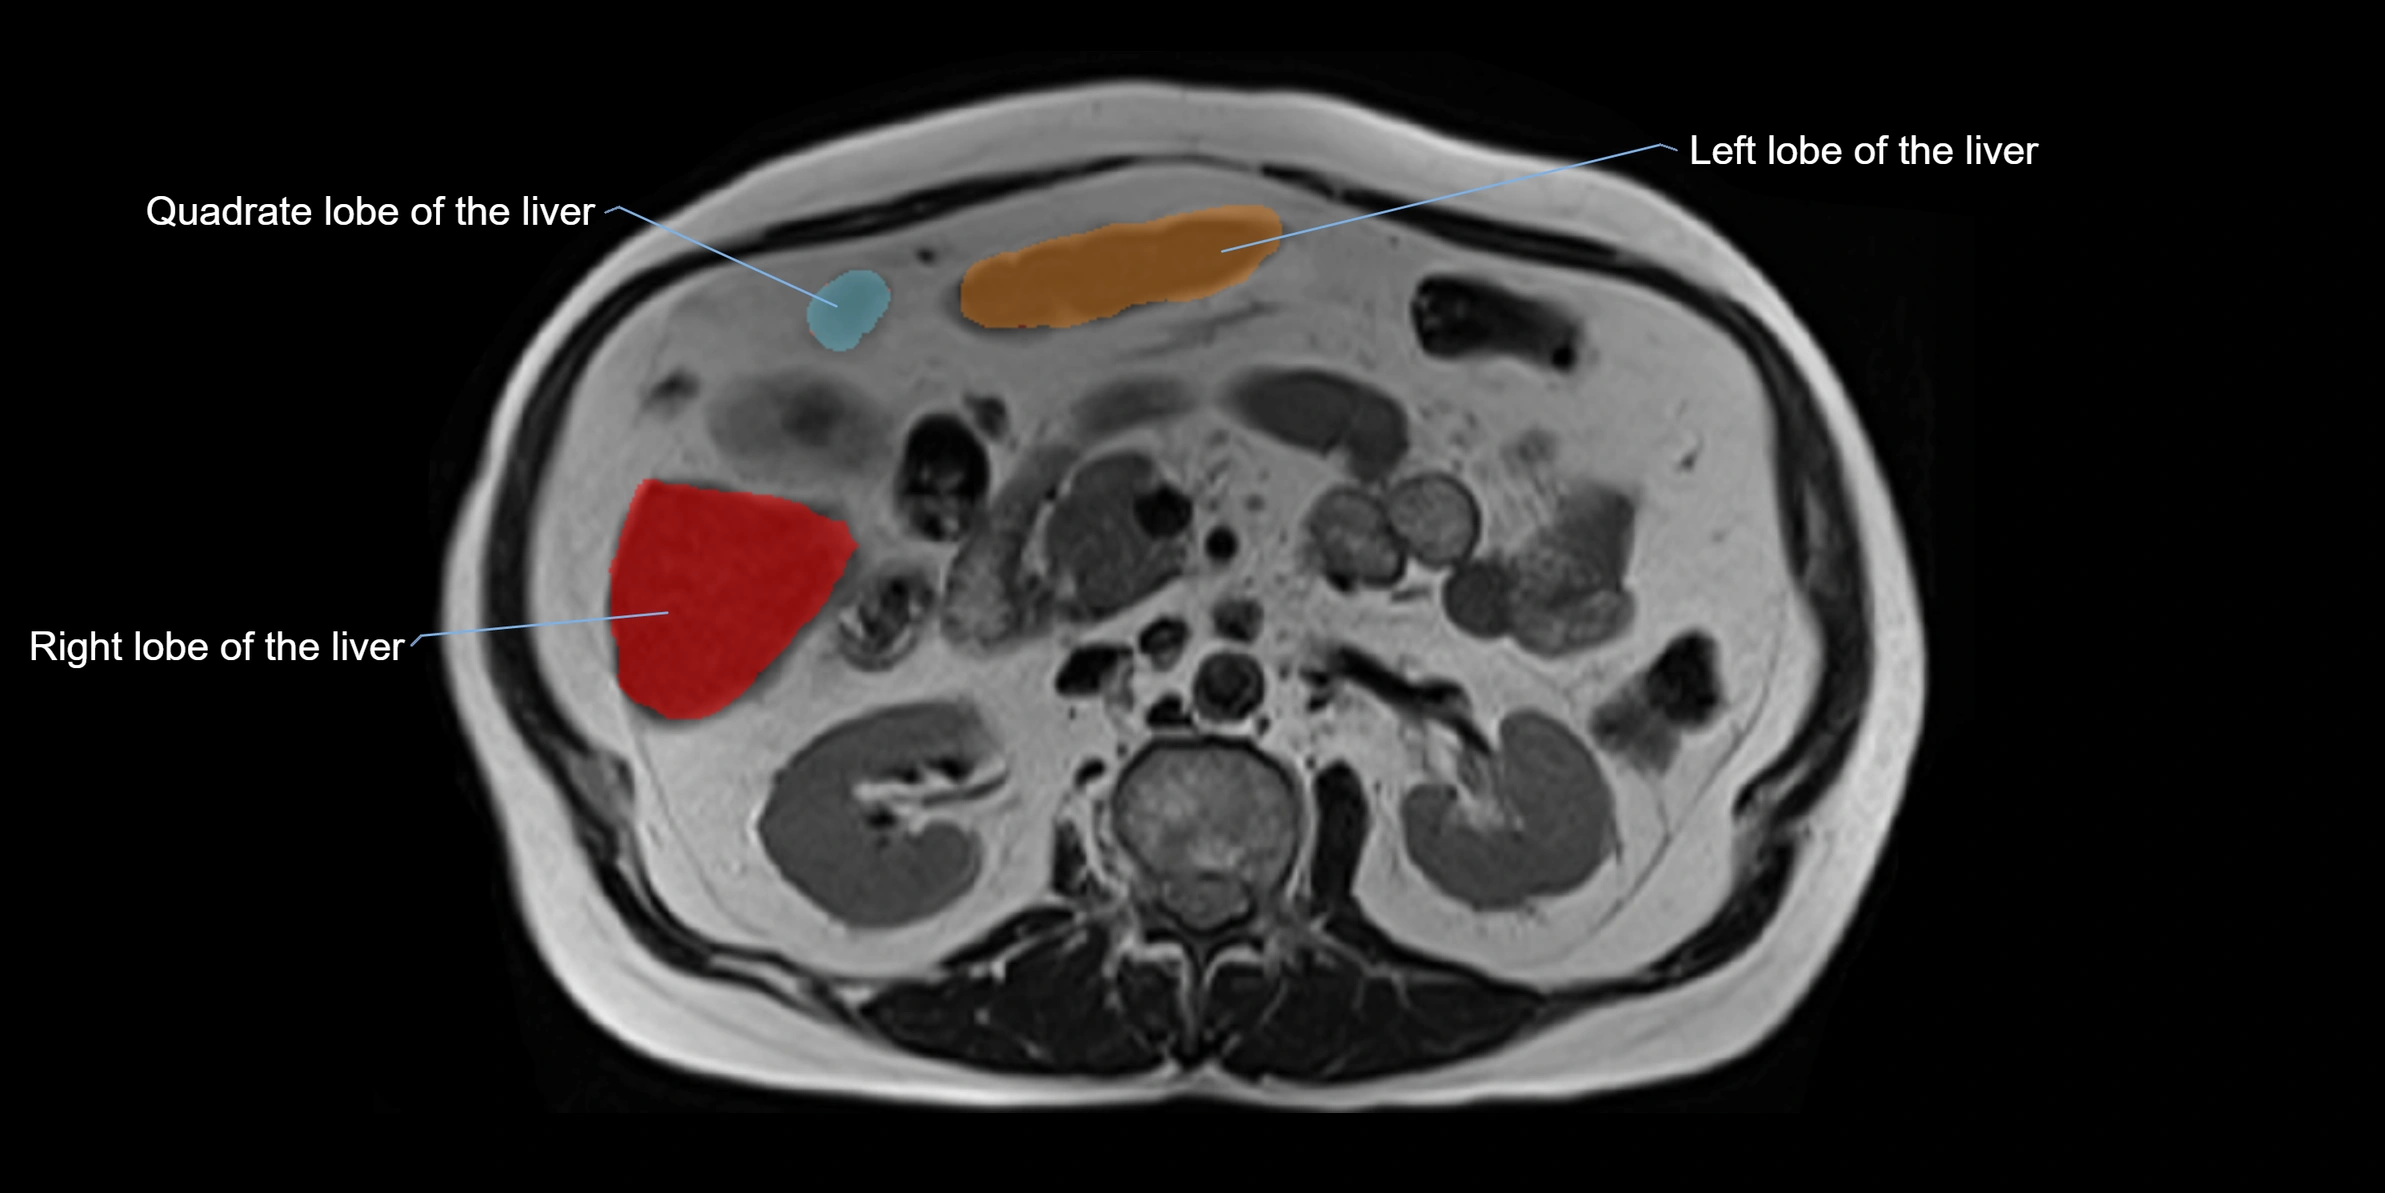

MRI image

image